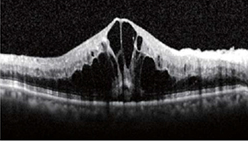

網膜の層構造を断面的に観察でき、黄斑浮腫の状態がわかります。